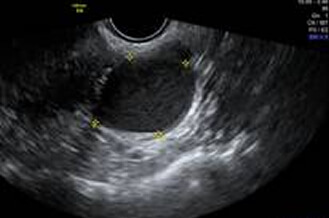

正常卵巢